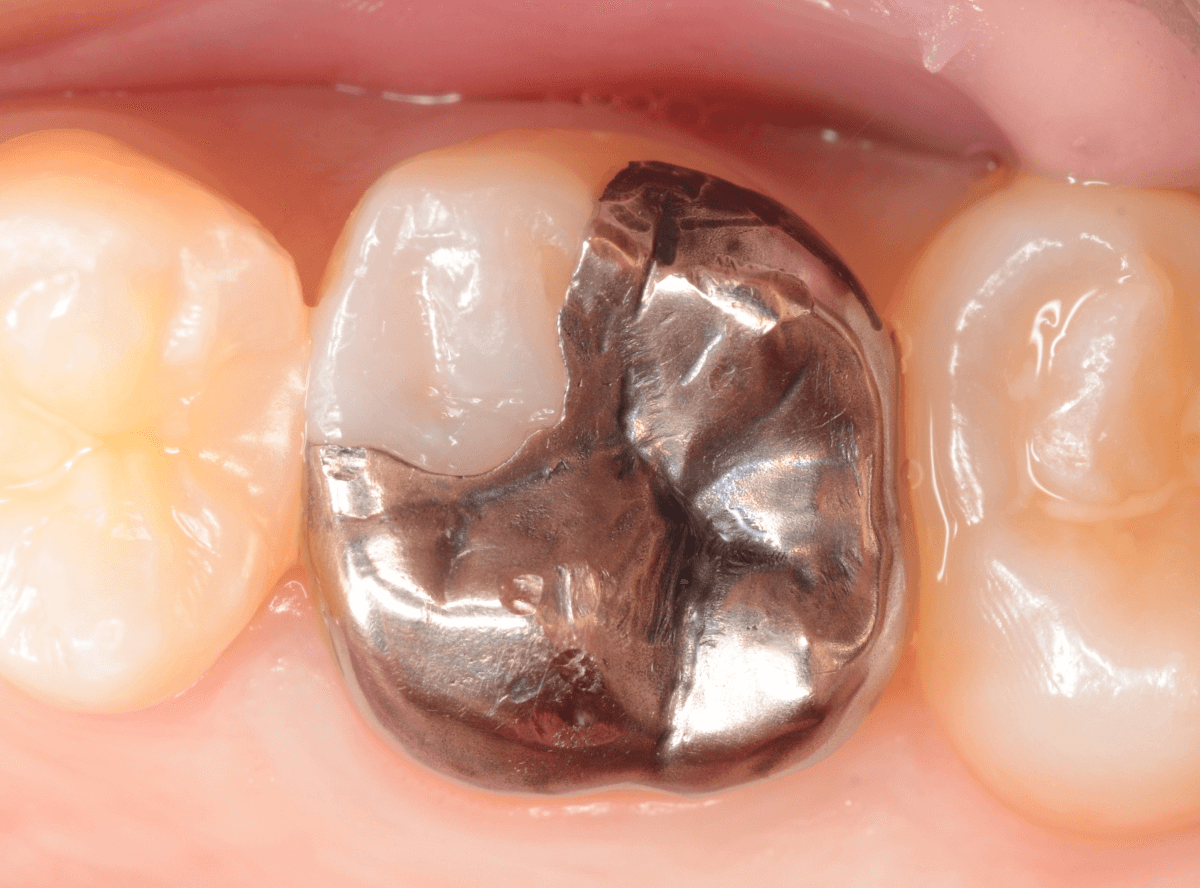

メタル・インレーとメタル・クラウンが入っていますね。

まずは、奥のメタル・クラウンを外します。

治療前後の写真になります。

やはり、印象が大きく変わりますね。